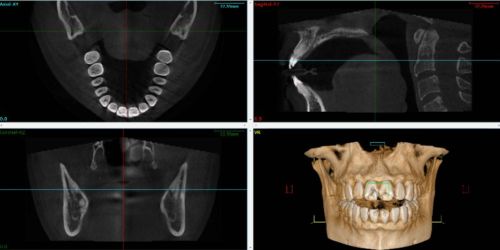

Le Cone Beam utilise un faisceau de rayons X conique et de largeur constante. Le principe est identique à celui de la radiologie conventionnelle dont se servent les praticiens tous les jours. L’appareil effectue une rotation autour de l’objet examiné et réalise une projection sur un capteur numérique à chaque impulsion. Le cone beam permet d’obtenir directement le volume de l’objet par calcul informatique à partir des multiples projections 2D acquises durant la rotation de l’appareil. Les données de sortie sont au format DICOM2.

Pour faire une analyse des ATM3, il est recommandé de réaliser des scanners grand champ incluant l’intégralité des maxillaires. De plus, la qualité des fichiers est directement liée à la procédure de segmentation, il faut porter une attention sur l’intégrité des données au niveau des structures osseuses de l’ATM.